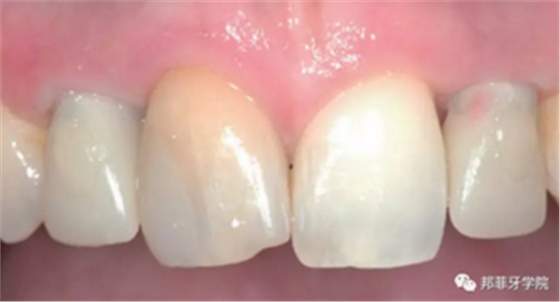

最終印模采用個(gè)性化印模柱,記錄穿齦輪廓(圖13)。CAD/CAM個(gè)性化基臺(tái)精確就位(圖14)。全瓷冠水門汀固位(圖15)。

圖 15-1:六個(gè)月后復(fù)查

圖 15-2:六個(gè)月后復(fù)查